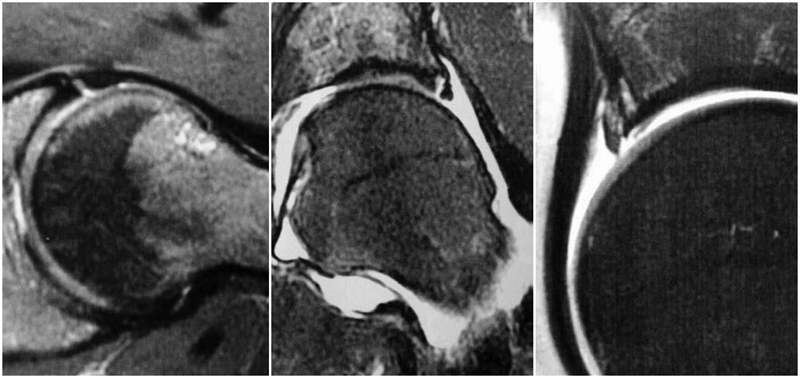

对于髋关节撞击综合征的诊断,不同于髋关节骨性关节炎或者股骨头坏死的患者,不能仅仅通过普通的X光片和双髋关节核磁共振就能确诊,因为造成髋关节撞击综合征的异常骨性凸起通常位于髋臼或者股骨头颈结合区的前外侧,所以临床上常规的髋关节正侧位片上,这个骨性异常的区域恰恰被遮挡了起来,在X光片上成了重叠的影像。在诊断髋关节撞击综合征,会采用一些特殊的影像拍摄方法。对于X光的选择,推荐进行骨盆正位相联合蛙式侧位或Dunn位像。对于盂唇损伤的诊断主要依赖于核磁共振检查,由于双髋关节核磁共振放大率以及扫描方向的问题,不足以判断盂唇的状态,一般需要进行单髋关节核磁共振扫描。

图6 摘自Tannast M, Siebenrock KA, Anderson SE. Femoroacetabular impingement: radiographic diagnosis-what the radiologist should know[J]. Am J Roentgenol, 2007,188(6):1540-1552

图7 摘自Stoller DW. Magnteic Resonance Imaging In Orthopaedics And Sports Medicine[M]. 3rd Edition, 2007